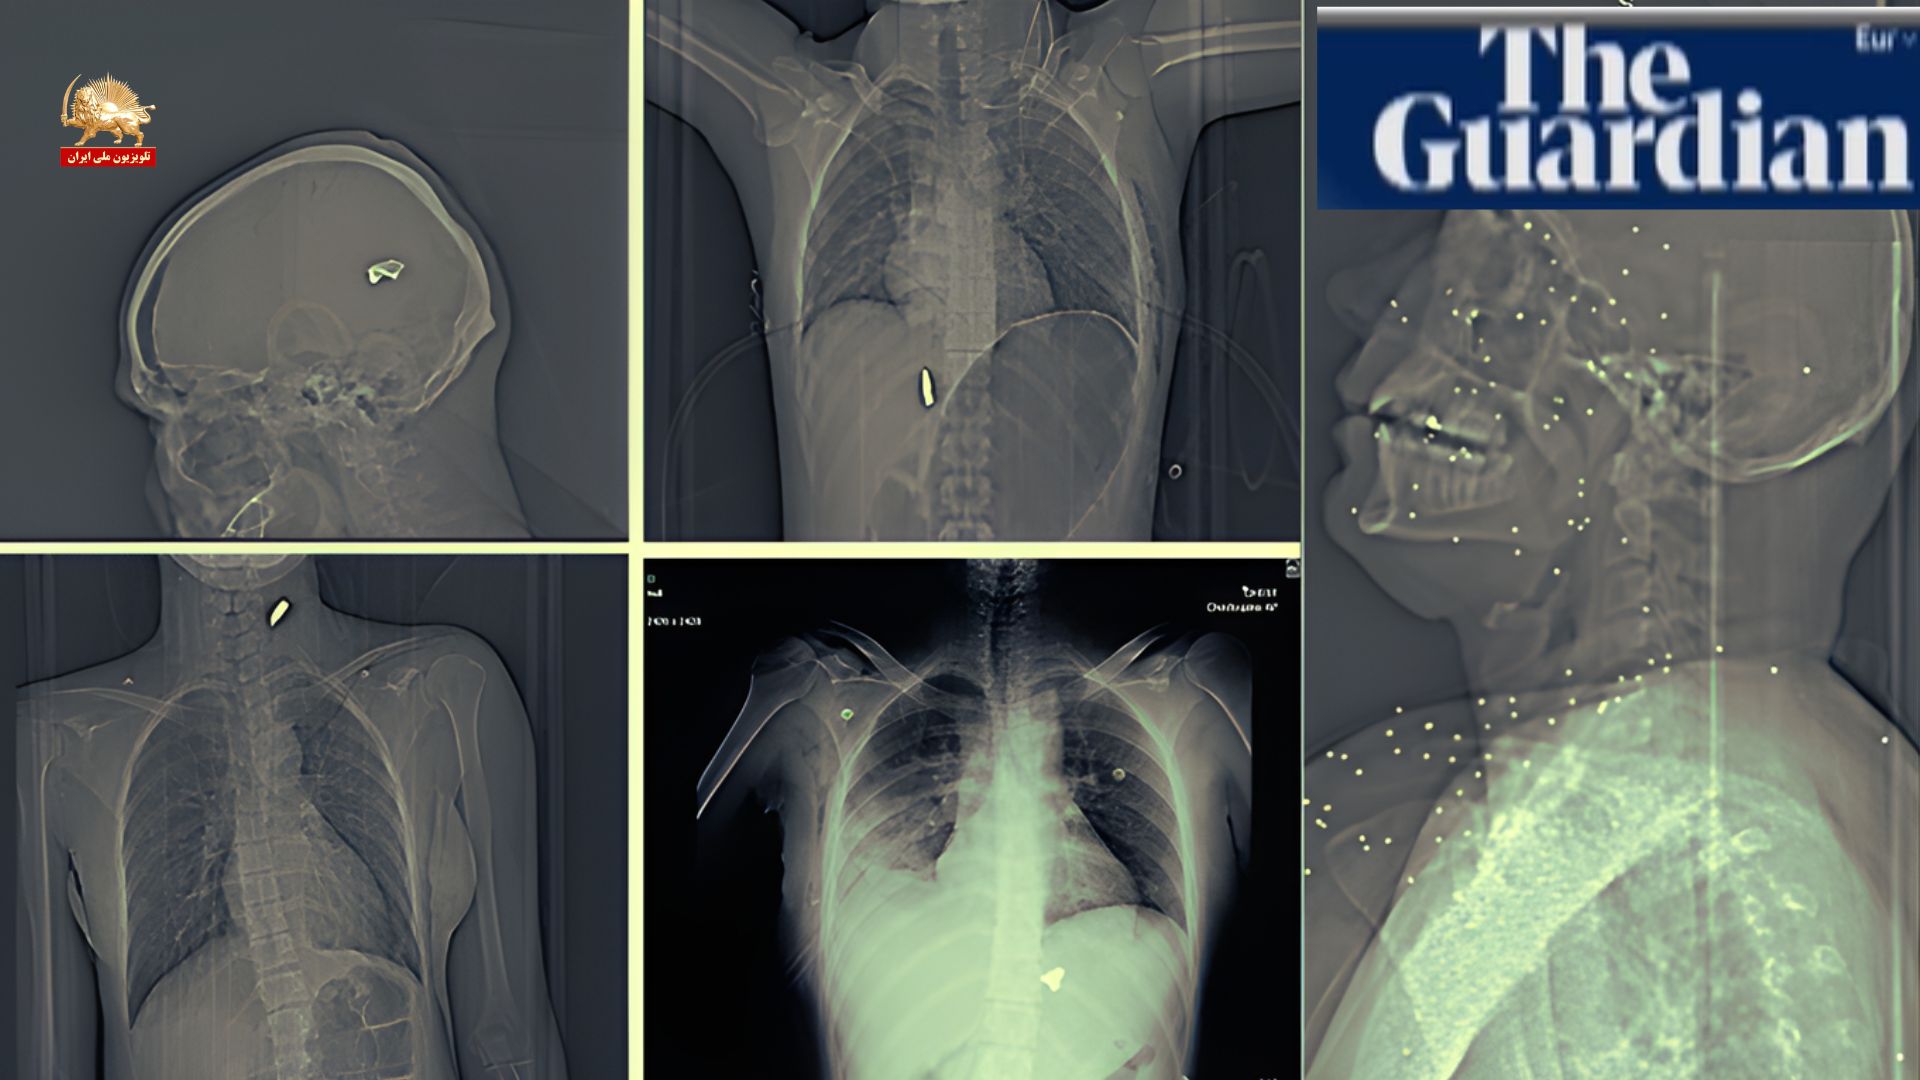

گاردین شواهد پزشکی جدید از سرکوب خونین قیام دیماه منتشر کرد: هدف‌گیری عمدی نقاط حیاتی بدن

گزارش گاردین: اشعه ایکس و سی‌تی اسکن‌ها گستردگی جراحات فاجعه‌بار ناشی از گلوله‌های ساچمه‌ای و کالیبر بالا در اعتراضات ایران را نشان می‌دهد

روزنامه گاردین در گزارشی با عنوان «هدف‌گیری عمدی نقاط حیاتی بدن» شواهد پزشکی جدیدی از سرکوب خونین قیام دیماه منتشر کرد. گاردین نوشت: «اشعه ایکس گرفته شده پس از اعتراضات ایران، گستردگی جراحات فاجعه‌بار را نشان می‌دهد». این گزارش بر اساس ۷۵ مجموعه تصویر پزشکی (عمدتاً اشعه ایکس و سی‌تی اسکن) از یک بیمارستان تهیه شده که بیماران را درمان کرده است.

کارشناسان: سلاحهای به‌کار گرفته شده توسط نیروهای سرکوبگر رژیم آخوندی «سلاحهای با هدف کشنده» هستند

تصاویر نشان‌دهنده جراحات شدید به‌صورت و سینه ناشی از گلوله‌های ساچمه‌ای و گلوله‌های کالیبر بالا است. کارشناسان بالستیک و پزشکی این سلاحها را «سلاحهای با هدف کشنده» توصیف و تأکید کردند که در فاصله نزدیک، ساچمه مانند «۱۰۰ گلوله کوچک» عمل می‌کند.